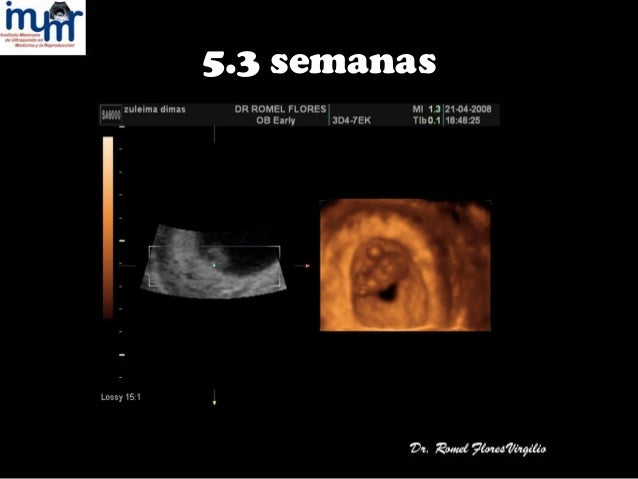

Ultrasonido bebe de 5 semanas de gestacion

Ultrasonido bebe de 5 semanas de gestacion-Estudios longitudinales demuestran que el ritmo cardíaco se incrementa con la edad gestacional, pasando de 100–115 latidos/min a las 56 semanas a 140–150 latidos/min a las 9–10 semanas 4,5 Respecto al cuerpo lúteo, como ya se ha mencionado, es identificable en más del 90% de mi caso es este tengo 6 semanas de embarazo y fue con mi ginecologa y no se logro ver el embrion, tengo miedo porque me dijo que podria ser un embarazo sin embrion, aparte no tengo sintomas solo cansansio y me dijo que en la semana 7 me aria otro ultrasonido para ver si ya aparecia el embrion tengo miedo soy primeriza y yo si quiero a mi bebe

Se estima que aproximadamente a las cinco o seis semanas de gestación, el corazón del bebé comienza a latir Justo en esos momentos, la frecuencia cardíaca del feto es de 80 a 85 latidos por minuto, considerándose así absolutamente normal Justo a partir de este momento, la frecuencia cardíaca aumentará su ritmo en alrededor de tres latidos por minuto por día, a lo largoEcografía de 5 semanas Cómo cambia tu cuerpo en la Semana 5 de embarazo A las 5 semanas de embarazo, y tras obtener un resultado positivo en tu test de embarazo – incluso antes, si ya habías empezado a sentir algún cambio en tu interior algo en ti va a cambiar para siempreA las 5 semanas de embarazo, el bebé tiene el tamaño de una semilla de manzana Sí, tu embrión ahora puede ser comparado Aunque en la semana cinco del embarazo, es un pequeño de 0,13 pulgadas de corona a crápula y el bebé se está preparando para continuar su crecimiento indetenible hasta la última semana de embarazo